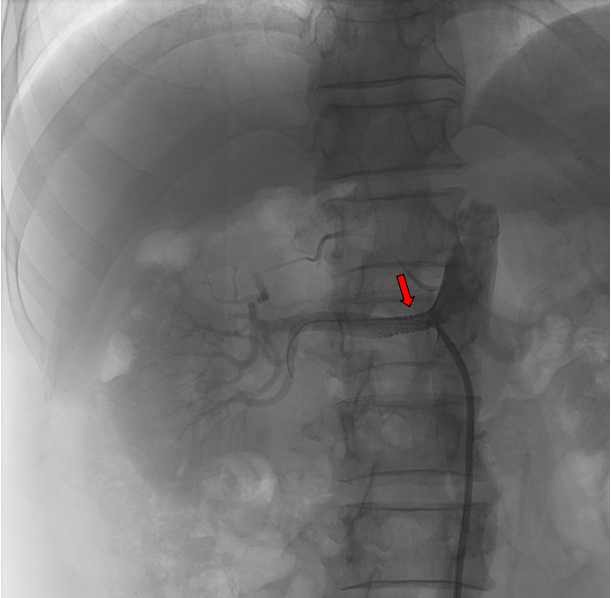

患者于4月9日上午送介入手术室行右肾动脉支架置入术。术中造影显示右肾动脉起始段明显狭窄,狭窄约90%,予置入肾动脉裸支架(7*19mm)后,造影显示右肾动脉狭窄解除,支架扩张良好,右肾灌注恢复。

1be37420733881ca3160ed50f975a4e.png

红色标记为支架置入前,右肾动脉明显狭窄